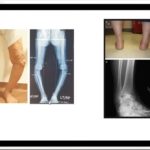

Leg Length Discrepancy Management

Assessment of Deformities in Lower Limbs